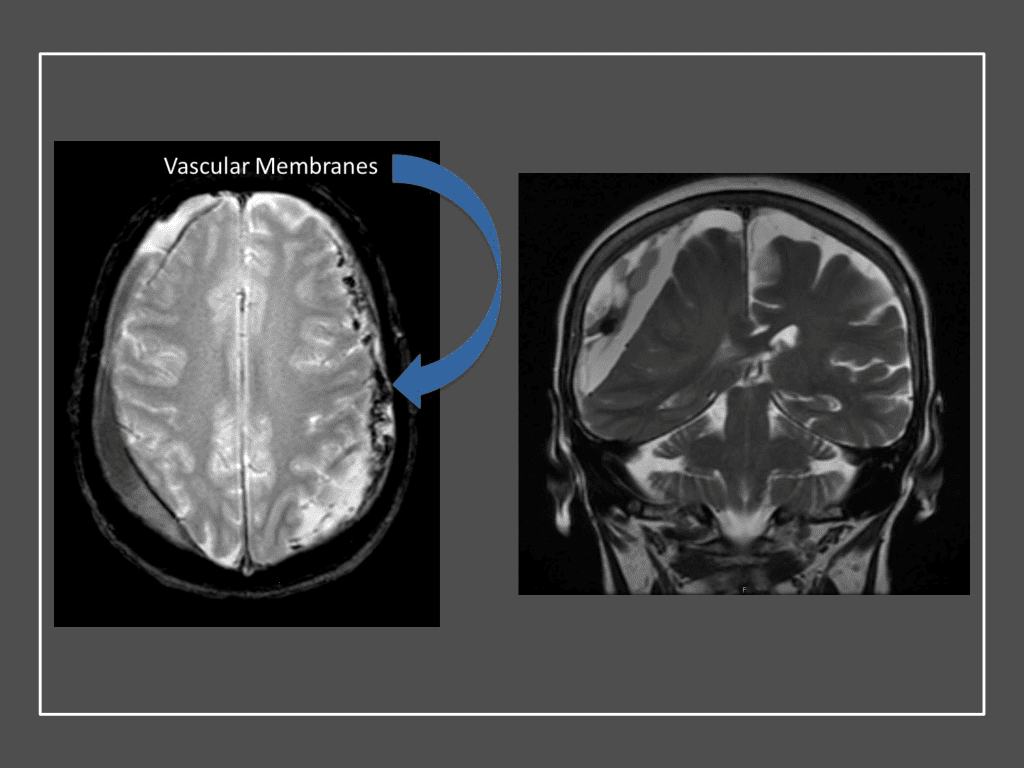

Figure 7. Neovascularized membranes within cSDH

Although conventional surgical methods, such as burr hole irrigation or observation in asymptomatic or minimally symptomatic patients have been the mainstay of treatment, middle meningeal artery (MMA) embolization has emerged as a promising adjunctive or alternative treatment. MMA embolization is a neuroendovascular technique which involves placing a microcatheter into the Middle Meningeal Artery, most commonly on the side of the cSDH (occasionally, bilateral embolization has been recommended for larger or bilateral collection. Embolization of both the anterior (frontal) and posterior (parietal) division is performed using a variety of embolic materials (liquid NBCA, Onyx, coils), although polyvinyl alcohol particles of <250 microns are most commonly used to achieve distal penetration and occlusion of the pre-capillary and capillary beds. The micro-leakage of blood and transudative proteinaceous inflammatory fluid in these inflammatory membranes is creating an imbalance in cycle of resorption and preventing resolution or promoting recurrence or growth of these cSDH collections and associated mass effect and midline shift.